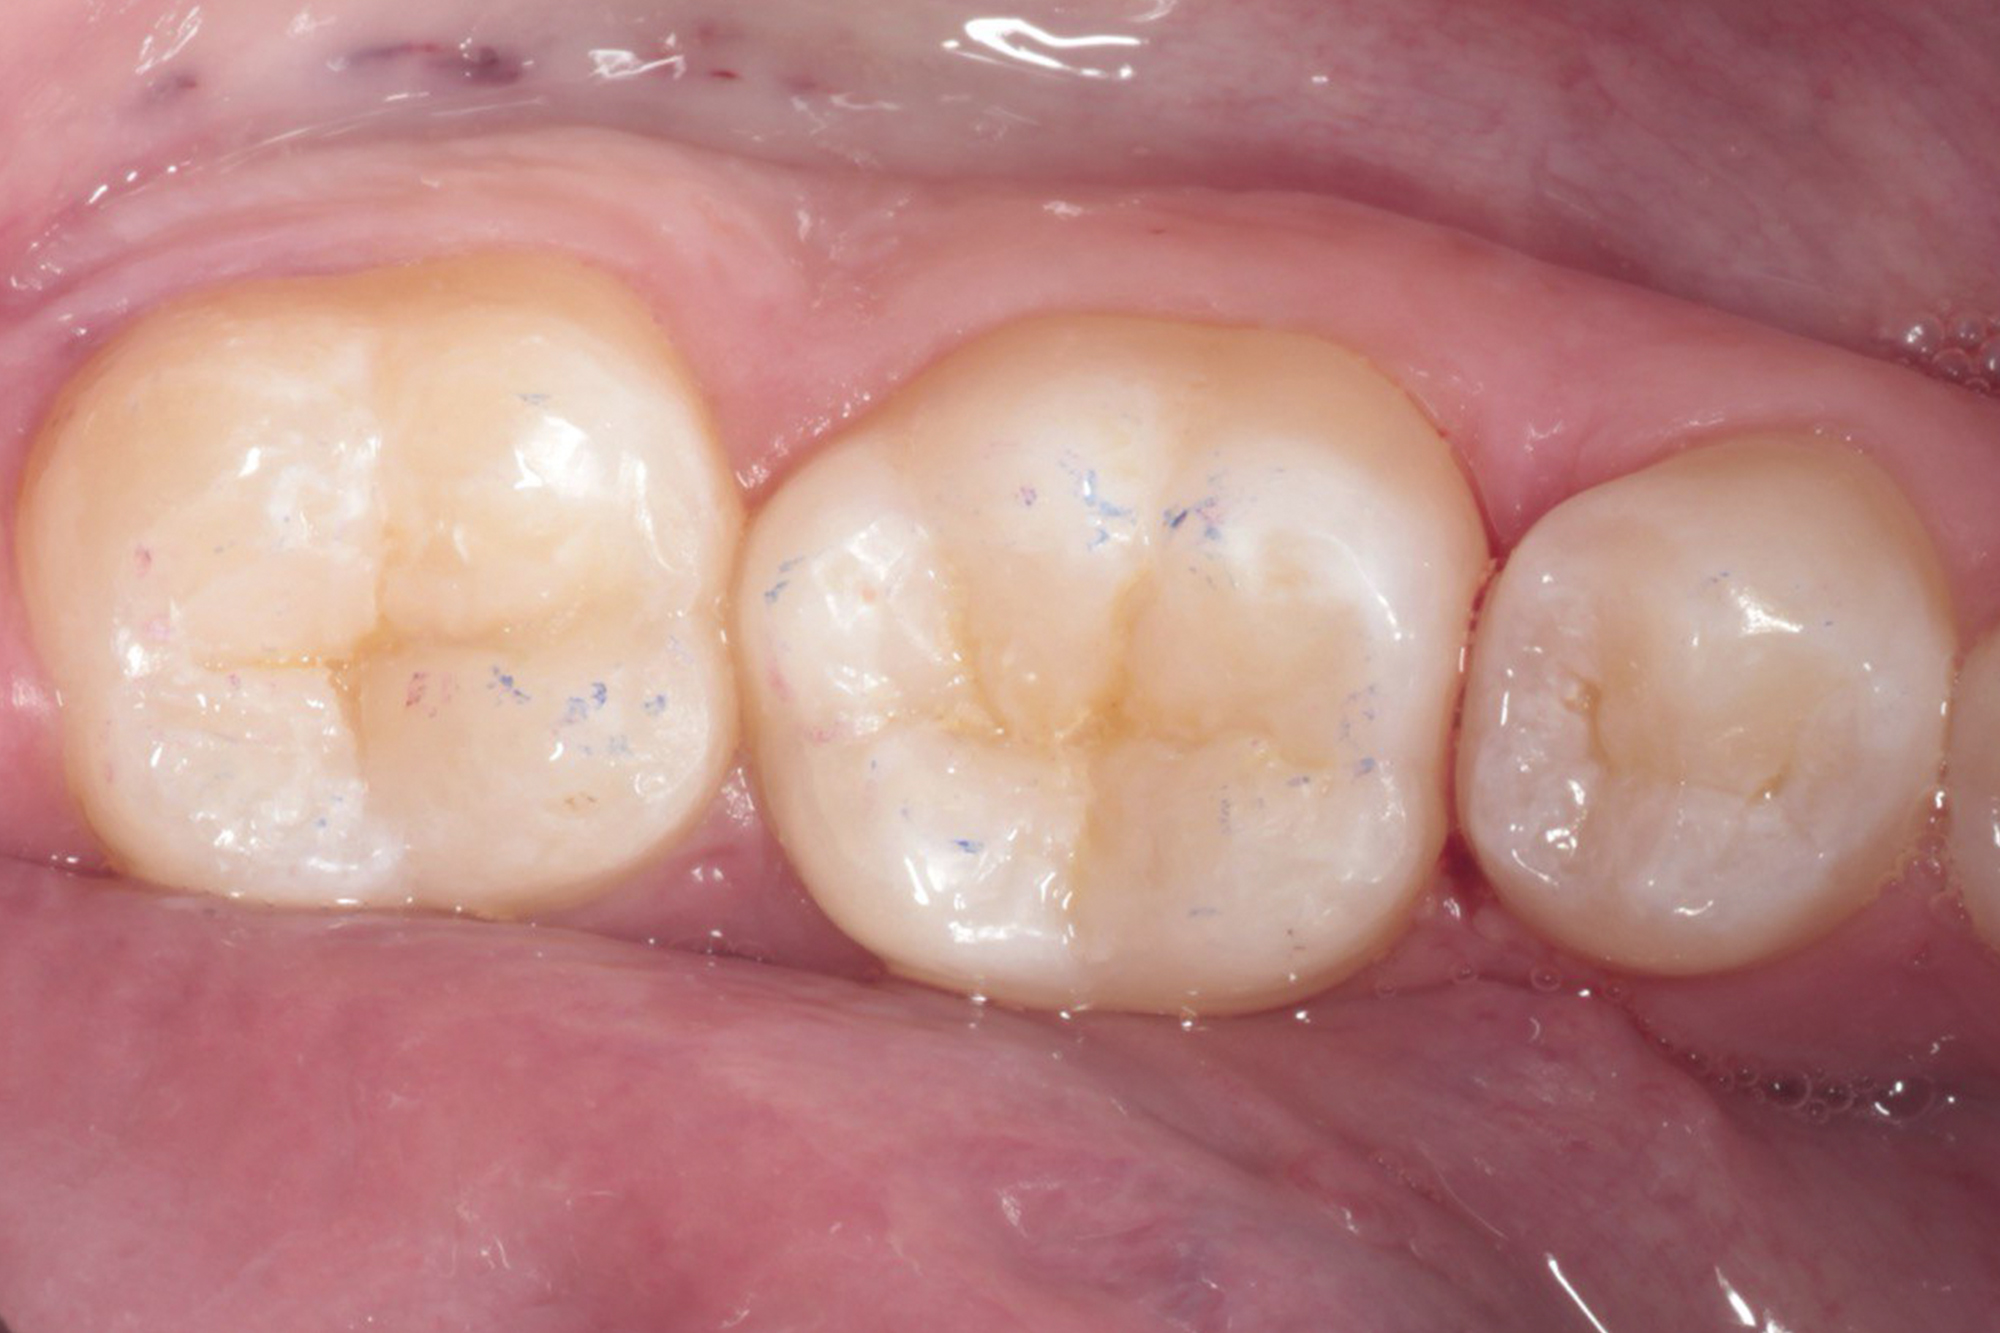

Наши работы